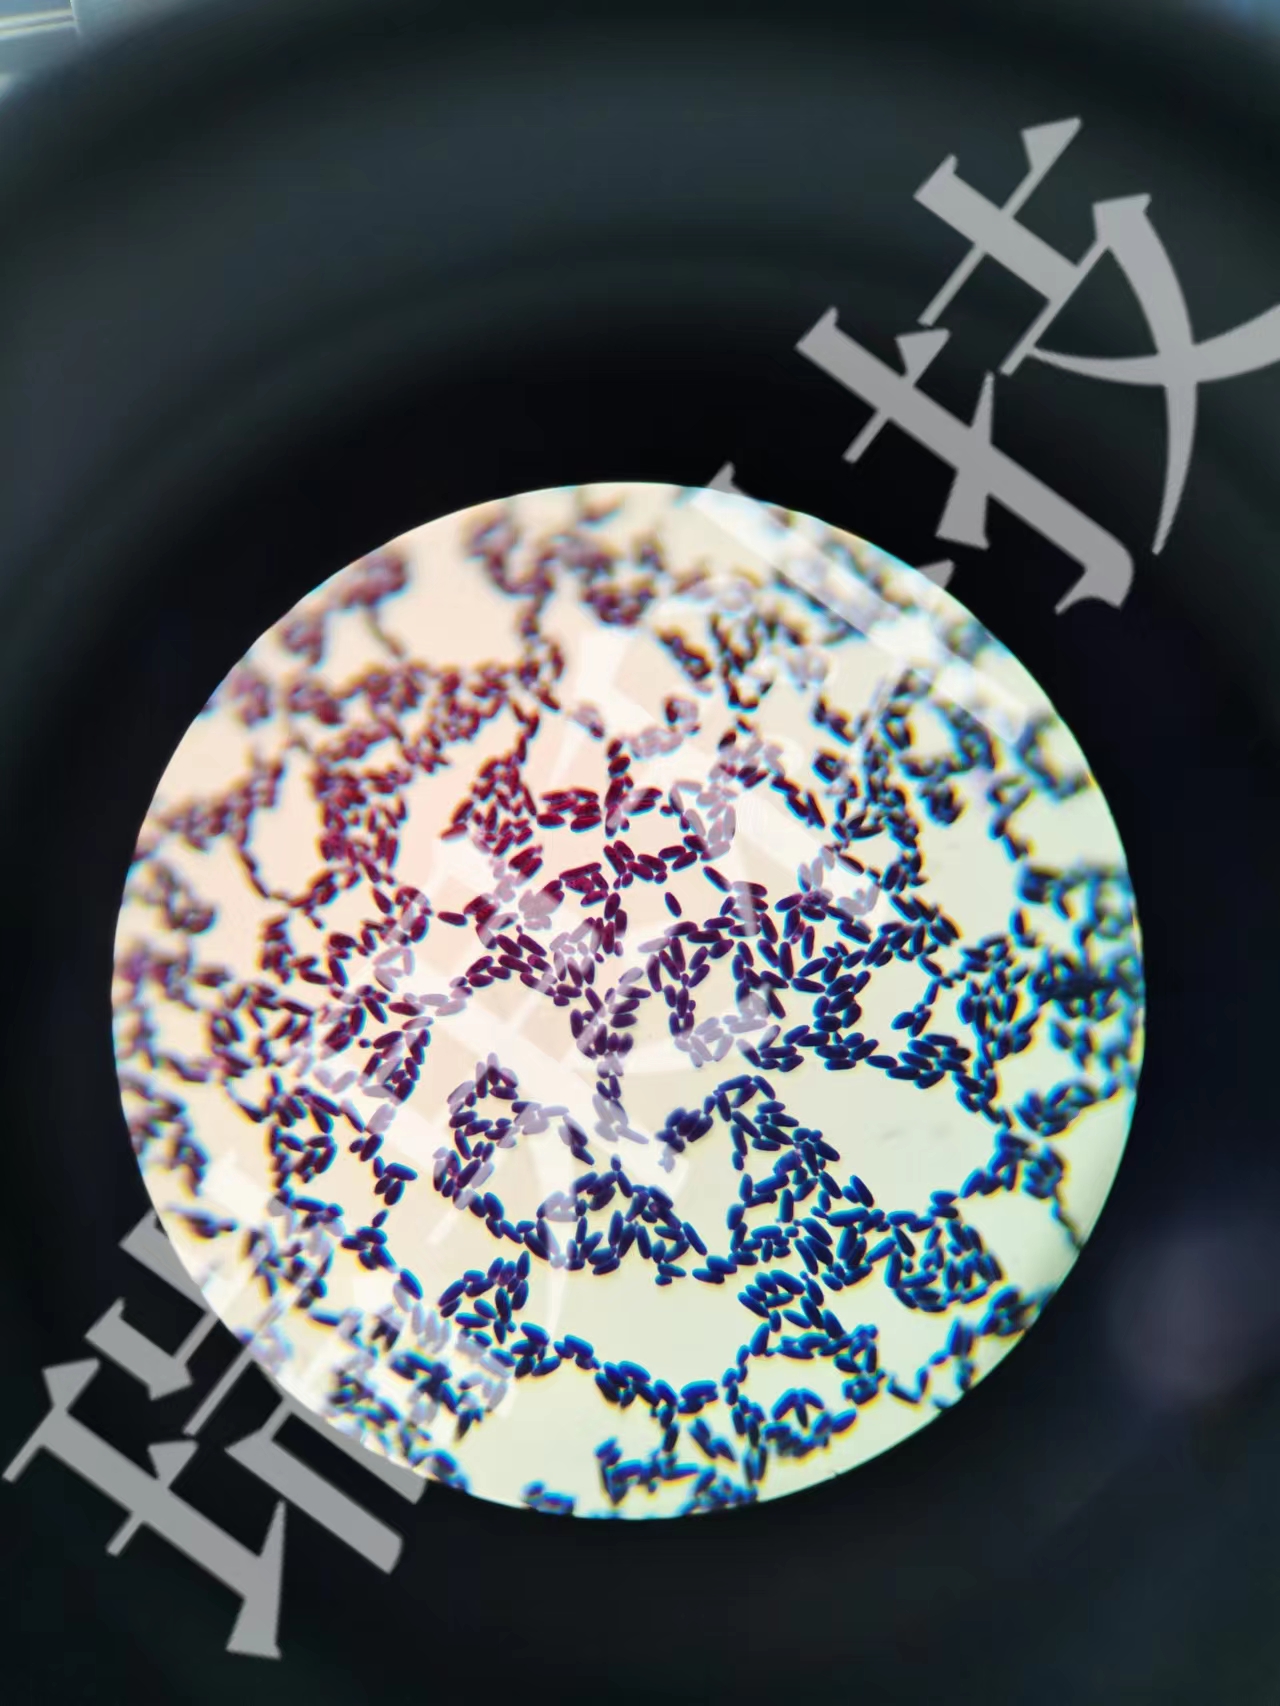

酵母菌革蘭氏染色